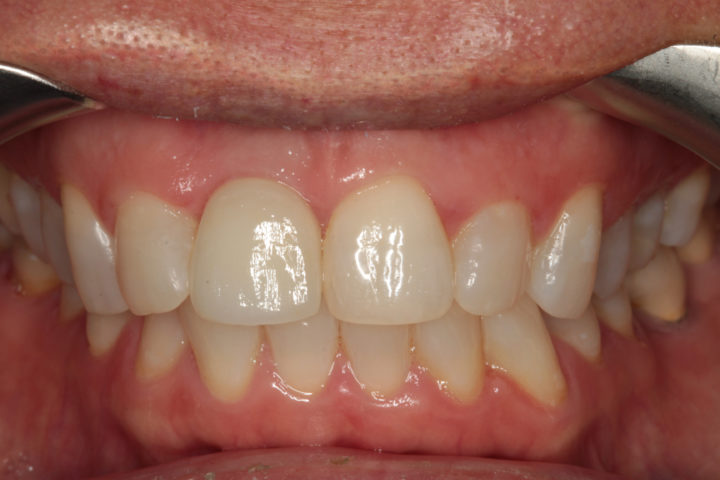

Risultato frontale:

Dopo l’intervento di implantologia, il nuovo incisivo su impianto si integra perfettamente per forma, colore e funzione. Il sorriso risulta naturale, armonico e completamente riabilitato.